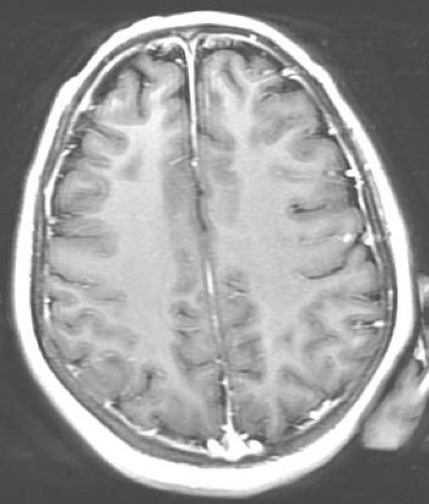

Magnetic resonance imaging scans of the brain were obtained on day 10 of hospitalization. The results demonstrated mild smooth dural enhancement after LP, without evidence of acute infarct, hemorrhage, mass, or hydrocephalus (Figure 1).

Figure 1. Magnetic resonance imaging scans of the brain with contrast (left) and without contrast (right), obtained on hospital day 10, showed mild smooth dural enhancement after LP. No evidence of acute infarct, hemorrhage, mass, or hydrocephalus was present.